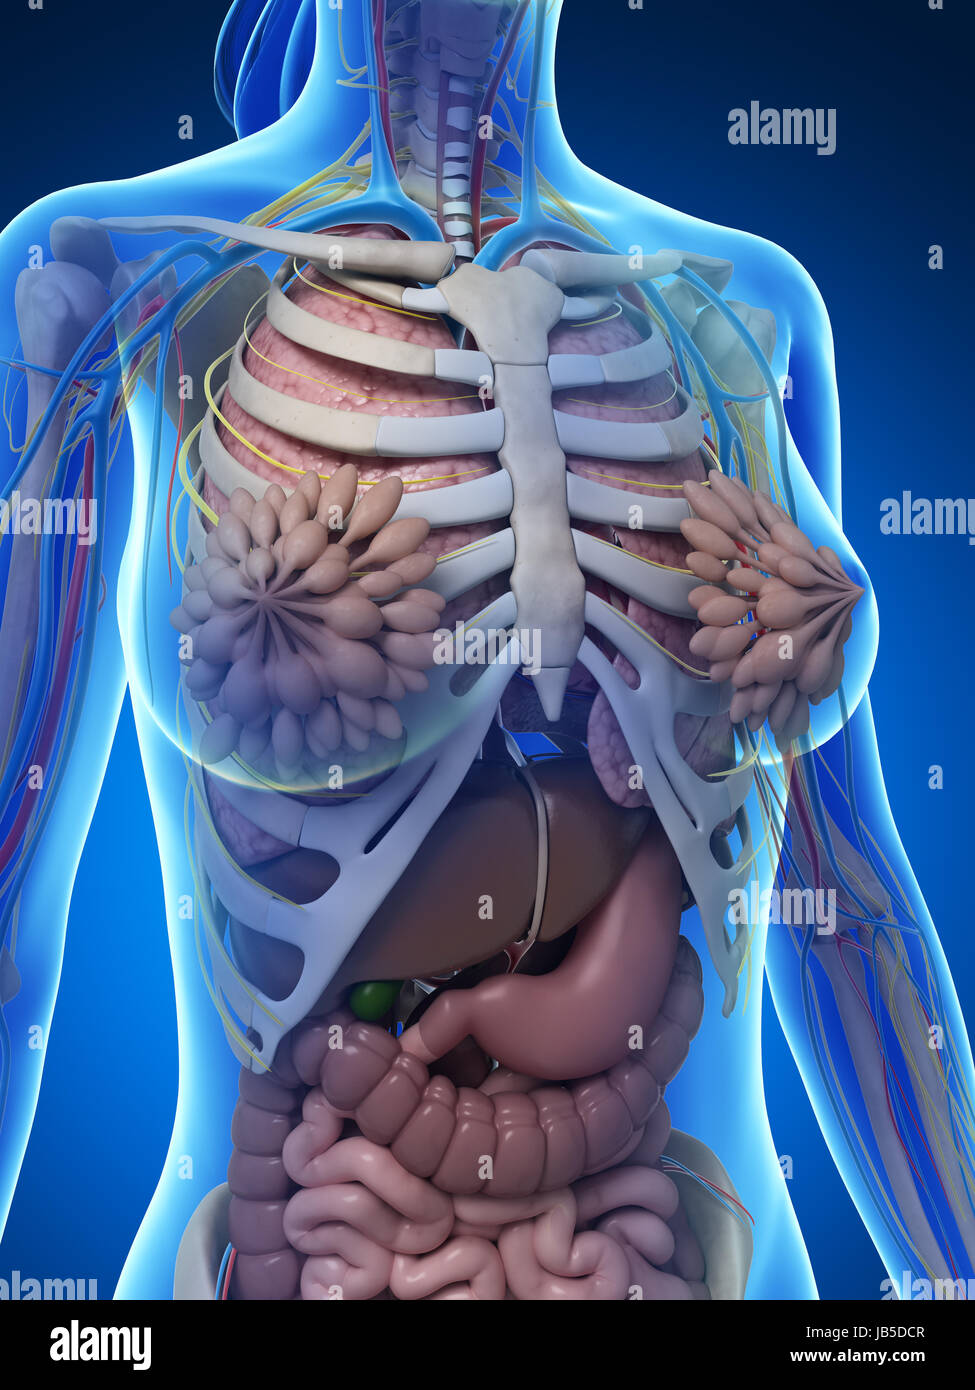

female anatomy art Complete female anatomy 3d model

If you are searching about Female Anatomy Photograph by Pixologicstudio/science Photo Library you’ve visit to the right page. We have 35 Pics about Female Anatomy Photograph by Pixologicstudio/science Photo Library like Female Anatomy Art Print Women Body Torso Drawing Illustration Modern, Female anatomy, artwork Stock Photo - Alamy and also Female Anatomy Photograph by Pixologicstudio/science Photo Library. Read more:

fineartamerica.comFemale Anatomy, Artwork Stock Photo - Alamy

fineartamerica.comFemale Anatomy, Artwork Stock Photo - Alamy

fineartamerica.comFemale Anatomy, Artwork Stock Photo - Alamy

fineartamerica.comFemale Anatomy, Artwork Stock Photo - Alamy

www.alamy.comFemale Anatomy, Artwork Stock Photo - Alamy

www.alamy.comFemale Anatomy, Artwork Stock Photo - Alamy

bocadowasubo.github.ioFemale Anatomy, Artwork Stock Photo - Alamy

bocadowasubo.github.ioFemale Anatomy, Artwork Stock Photo - Alamy

fineartamerica.comFemale Anatomy, Artwork Stock Photo - Alamy

fineartamerica.comFemale Anatomy, Artwork Stock Photo - Alamy

www.etsy.comFemale Anatomy, Artwork Stock Photo - Alamy

www.etsy.comFemale Anatomy, Artwork Stock Photo - Alamy

www.alamy.comFemale Anatomy, Artwork Stock Photo - Alamy

www.alamy.comFemale Anatomy, Artwork Stock Photo - Alamy

www.alamy.comFemale Anatomy, Artwork Stock Photo - Alamy

www.alamy.comFemale Anatomy, Artwork Stock Photo - Alamy

fineartamerica.comFemale Anatomy, Artwork Stock Photo - Alamy

fineartamerica.comFemale Anatomy, Artwork Stock Photo - Alamy

Female Anatomy, Artwork Stock Photo - Alamy

www.alamy.comFemale Anatomy, Artwork Stock Photo - Alamy

www.alamy.comFemale Anatomy, Artwork Stock Photo - Alamy

www.etsy.comFemale Anatomy, Artwork Stock Photo - Alamy

www.etsy.comFemale Anatomy, Artwork Stock Photo - Alamy

www.alamy.comFemale Anatomy, Artwork Stock Photo - Alamy

www.alamy.comFemale Anatomy, Artwork Stock Photo - Alamy

www.alamy.comFemale Anatomy, Artwork Stock Photo - Alamy

www.alamy.comFemale Anatomy, Artwork Stock Photo - Alamy

Female Anatomy, Artwork Stock Photo - Alamy

www.alamy.com3d Rendered Illustration Of The Female Anatomy Stock Photo - Alamy

www.alamy.com3d Rendered Illustration Of The Female Anatomy Stock Photo - Alamy

fineartamerica.com3d Rendered Illustration Of The Female Anatomy Stock Photo - Alamy

fineartamerica.com3d Rendered Illustration Of The Female Anatomy Stock Photo - Alamy

pixels.comFemale Anatomy, Artwork Stock Photo - Alamy

pixels.comFemale Anatomy, Artwork Stock Photo - Alamy

www.alamy.comFemale anatomy art print women body torso drawing illustration modern. Female anatomy photograph by pixologicstudio/science photo library. Female anatomy, artwork stock photo

www.alamy.comFemale anatomy art print women body torso drawing illustration modern. Female anatomy photograph by pixologicstudio/science photo library. Female anatomy, artwork stock photo